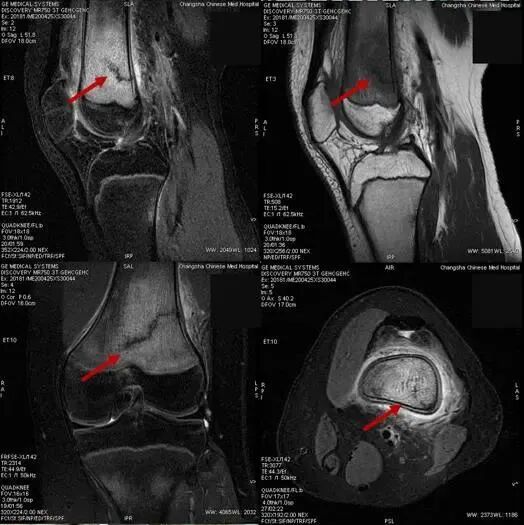

近日,湖南省长沙市某医院陆续诊断了7例“应力性骨折”患者,7名患者都是刚刚返校的初三学生。

李政介绍,骨折一般分为创伤性骨折病理性骨折两大类,应力性骨折又称“疲劳性骨折”,属于创伤性骨折一类,也可以说是“报复性”运动损伤,既因为长时间不运动或运动量较少,突然增加超运动量或短期内增加大量的运动,肌肉耐力超过极限,肌肉协调能力下降,保护能力减弱,使部分肌肉、韧带损伤,而此时运动应力易集中某段骨骼,造成所谓的“应力性骨折”或“疲劳性骨折”,长期减少运动本身也易使骨骼的韧性、强度减弱。应力性骨折通过普通X线片往往无法发现问题,容易发生漏诊,需要结合病史、查体,并配合磁共振检查来确诊诊断。